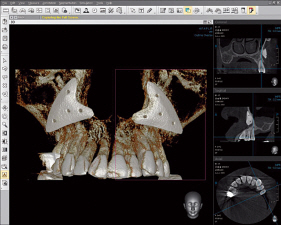

La radiología dental 3D ofrece al odontólogo informaciones muy detalladas para un diagnóstico más preciso y una mayor precisión en el tratamiento. La radiografía 3D le ofrece una visión más completa de la anatomía facial - prácticamente desde cualquier ángulo y perspectiva. Algo imposible de ver con imágenes 2D.

La radiología dental 3D es rápida y sencilla: en tan sólo segundos de escaneado le ofrece un estado completo de la zona bucal, maxilar y dental del paciente. Estas informaciones precisas y extensas pueden ayudarle a asesorar aun mejor a sus pacientes.

Nada permanece oculto: con la radiología dental obtendrá una imagen completa de la estructura oral, incluidos los huesos maxilares, estructuras blandas y nervios - todo ello con un único escaneado

Diferencias entre la radiografía 3D y la radiografía convencional

Radiografías más rápidas, sencillas y precisas - y en la más alta calidad 3D